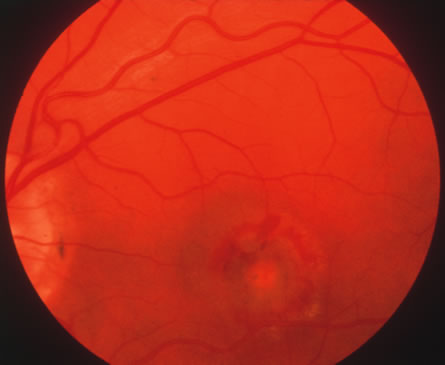

In primary ocular HSV infections, a severe follicular conjunctivitis with regional adenopathy is present. Vesicles may appear on the eyelid skin or lid margin, producing blepharitis (Fig. 3). Corneal involvement initially takes the form of a superficial punctate keratitis, which may progress to dendritic or geographic ulceration. Stromal infiltrates and uveitis are less common and relatively mild in primary disease. In uncomplicated cases, lesions usually heal completely in 2 to 3 weeks without scarring. Most cases of ocular HSV are recurrences. Recrudescent ocular herpes may take the form of dendritic or geographic ulcers, recurrent erosions, interstitial or disciform stromal keratitis, and anterior uveitis.3 HSV may also be an agent of retinitis and acute retinal necrosis (Fig. 4).

The acute retinal necrosis (ARN) syndrome is most often caused by the herpes zoster virus, although occasionally it may be a result of herpes simplex infection.12 It is typically described in healthy patients although association with immunosuppressed patients has also been described. Granular, nonhemorrhagic areas of retinal necrosis may be observed in the fundus, often rapidly coalescing with resulting blindness often caused by retinal detachment. There is often an associated vasculitis and vitritis. In immunocompromised patients VZV or HSV retinitis may also take the pattern of progressive outer retinal necrosis (PORN) (Fig. 6). PORN differs from ARN in that the former is multifocal, localized to the outer retina, and is less often associated with vasculitis and vitritis.